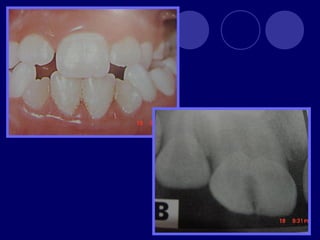

• 45.

AMELOGENESIS IMPERFECTA  Hipoplásico: Zonas ausentes de esmalte  Afecta más a caras vestibulares  Esmalte: blanco amarillento y marrón claro, consistencia dura, fosas y surcos oscuras, delgado  Hipocalcificado:  Cualitativo  Esmalte frágil, fácil de desprender  Rx: falta de contacto entre dentina, esmalte  Hipomaduro:  Disminución en el contenido mineral  Esmalte blando y rugoso, veteado de blanco a marrón (esmalte en copos de nieve)  Más frecuente en caras vestibulares y dientes superiores

DISPLASIA AMBIENTAL DEL ESMALTE HIPOPLASIA POR INGESTA DE FLÚOR: fluorosis, manchas opacas, esmalte sin brillo(leve=lechoso, graves=amarillo/café) .